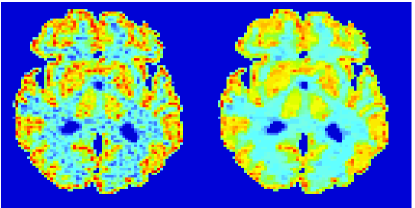

In the images shown in the figures we illustrate the calculated uptake rates of the FDG. Images for the CMRGlc can be obtained by directly scaling . In figure 1 we compare the result of using Patlak and TV-Patlak for estimating the uptake rates with respect to no noise, noise in the input function, Poisson noise in the sinogram, and finally with respect to the case in which the irreversibility assumption is violated but without noise in the sinogram or input data. In each case the histogram of the relative errors is given on the left, the Patlak image in the middle and the TV-Patlak on the right. The different scales in the histograms are due to the total number of results illustrated. When there is no noise (triples and ) the histogram illustrates results over all voxels but only one simulation, while for the noisy simulations the results are for all voxels over all realizations of the noise. The TV-Patlak images are more homogeneous in all cases and the relative errors are smaller. The figures clearly show the improvements of employing the TV-Patlak method as compared to using Patlak independently for each voxel. This is confirmed in figure 2 in which images with noise in the sinogram, positive and different noise levels in the input function are shown.